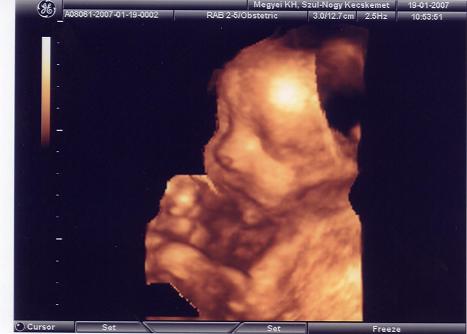

Képzeljétek, tegnap voltunk 4d-n, minden rendben, van kép, meg dvd is. Persze a lényeg a papír, meg amit a doki mondott, de már annyira vártam, hogy láthassam a kisfiunkat! Most csak egy képünk van, a többit a dvd-ről fogjuk megcsinálni. Ezt megpróbálom feltenni, ha sikerül.

Adatok:

BPD: 80 mm

AC: 282 mm (haskörfogat)

FL: 60 mm (combcsont)

HC: 294 mm (fejkörfogat)

OFD: 105 mm (homlok-tarkó közti távolság)

Hum: 51 mm (felkarcsont)

Ja, és a súlybecslés: 1901 g.

Ahogy néztem, minden kicsit előrébb van a koránál (31 hét), van ami a 34. hétre jellemző. De a szülés várható időpontja nem változott, továbbra is március 24. Annyira boldog voltam és vagyok még most is, de persze akkor hinném el, ha már itt lenne a kezemben.

Ja, és a nevét is kitaláltuk (végre): Balázs! Kép